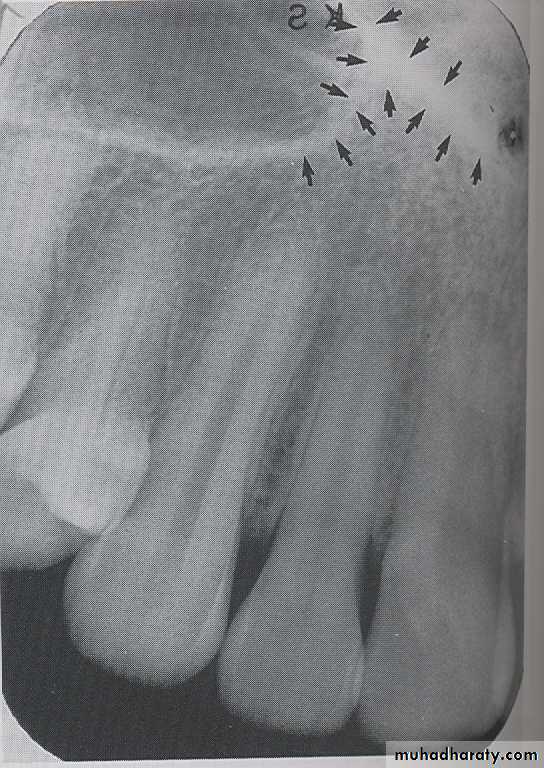

MYLOHYOID RIDGE

: The mylohyoid ridge is a linear prominence of bone located on the internal surface of mandible, its extended from the molar region downward and forward toward the lower border of mandibular symphysis and serves as the attachment site for the mylohyoid muscles. Radiographic appearance, mylohyoid ridge appears as a dense the radiopaque band that extends downward and forward from molar region.

SUB MANDIBULAR FOSSE:

Submandibular fosse is a scooped–out depressed area of bone located on the internal surface of mandible inferior to mylohyoid ridge. On periapical radiography the submandibular fosse appears as radiolucent area in the molars region below the mylohyoid ridge.